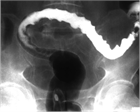

1. 虚血性大腸炎とは、動脈硬化や腸管内圧の亢進による腸管の虚血により生ずる粘膜傷害である。

1. 本症の病因は不明であるが、血圧低下、動脈硬化などの血管側因子と腸管内圧亢進などの腸管側因子がからみあい、腸粘膜あるいは腸管壁の血流低下を引き起こして虚血状態を作ると推定されている。